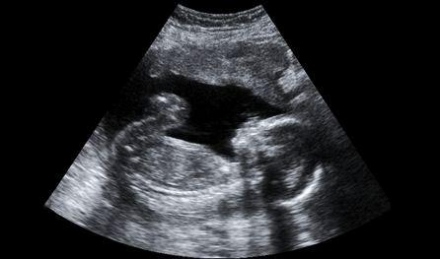

Mit mutat az ultrahang?

Az egyik legizgatottabban várt vizsgálat a gyermekvárás hónapjai alatt az ultrahang. Ennek a vizsgálatnak nemcsak komoly diagnosztikai jelentősége van, de betekintést nyújt a növekvő, várva-várt kicsi világába is, még akkor is, ha csak hagyományos...